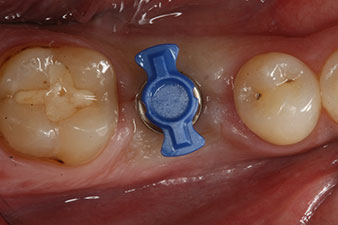

Tras la extirpación minuciosa del tejido de granulación, se incorporó el implante tal como se había planificado (blueSky, bredent).

El torque en el momento de la carga mecánica fue de 43 Ncm. Asimismo, después de atornillar un poste de medición especial adaptado al sistema de implante (SmartPeg), el valor ISQ se determinó con la sonda del módulo Osstell ISQ de W&H.

Este módulo Osstell ISQ que se encuentra disponible como accesorio para la unidad Implantmed de W&H y se acopla al motor de implantes (véase figura 11). El valor ISQ adimensional fue de 64 justo en el momento de la inserción en la dirección bucovestibular y de 68 en la dirección mesiodistal (valor máximo = 100).